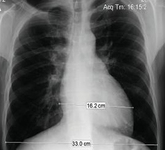

Ressonância nuclear magnética em um paciente com regurgitação pulmonar após reparo de tetralogia de Fallot. O paciente tem ventrículo direito restritivo e o coração é pequeno

De: Chaturvedi RR, Redington AN. Heart. 2007 Jul;93(7):880-9; usado com permissão